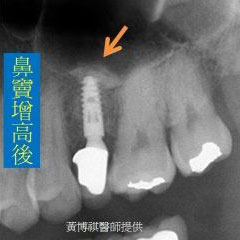

微創型鼻竇增高術是利用"鼻竇挺"輕輕將人工骨粉推入鼻竇腔。由連續X光片可以看到,人工骨 粉慢慢地被送進鼻竇腔中。 |

待完成鼻竇增高術後,便可植入適當長度的人工牙根。 |